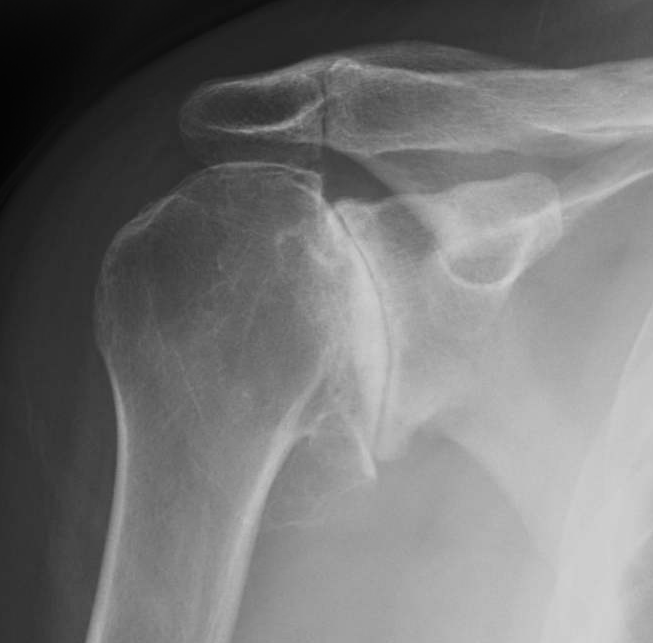

Diagnosis of Shoulder Arthritis

Diagnosing shoulder arthritis begins with a comprehensive physical examination, combined with advanced imaging and diagnostic tests. Your surgeon will assess your shoulder’s range of motion, strength, and any tenderness around the joint. Other diagnostic measures include:

- X-rays: To assess cartilage loss, joint space narrowing, and bone spurs.